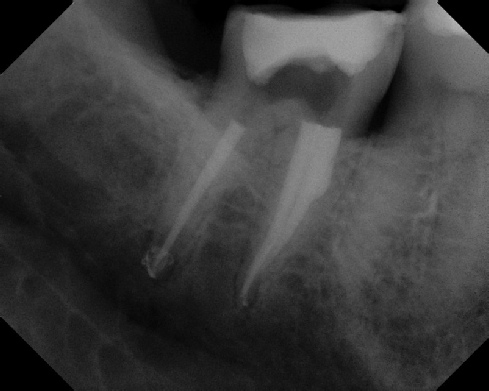

Pre-op Post-op 1 Post-op 2